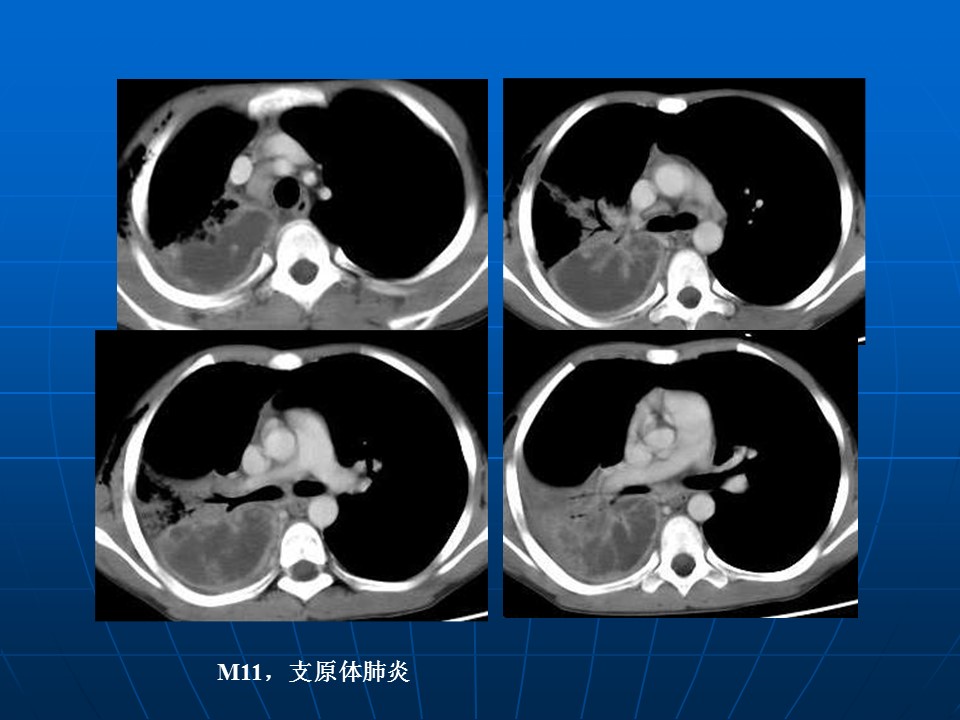

【PPT】早期肺癌易漏诊征象分析